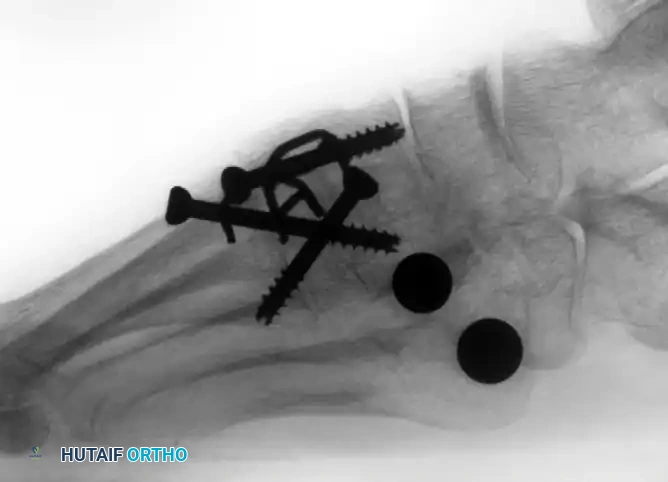

(Above: Anteroposterior and oblique radiographic appearance 10 months after a combined medial/middle column fusion with lateral tarsometatarsal ceramic interpositional arthroplasty. Note the preservation of the lateral joint space and stable seating of the spherical implants.)